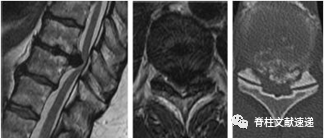

儿童急性钙化性椎间盘炎

椎间盘钙化在成人影像学中很常见,但有症状的钙化性椎间盘炎(也称为症状性或特发性椎间盘钙化)在儿童中并不常见。

患者症状主要发生在颈椎,颈部或背部疼痛、斜颈和活动受限最常见。

急性疼痛,自发缓解较快;神经系统症状不常见;治疗的主要方法是保守治疗。

图注:5岁女孩出现症状性儿童钙化性椎间盘炎,颈部疼痛3周,无外伤史。出现斜颈,活动受限。随访6个月后 CT图像显示突出部分的钙化点被吸收,C3/4髓核仅有微小的残余钙化(箭头)。3个月后疼痛几乎完全缓解,6个月随访时疼痛完全缓解。